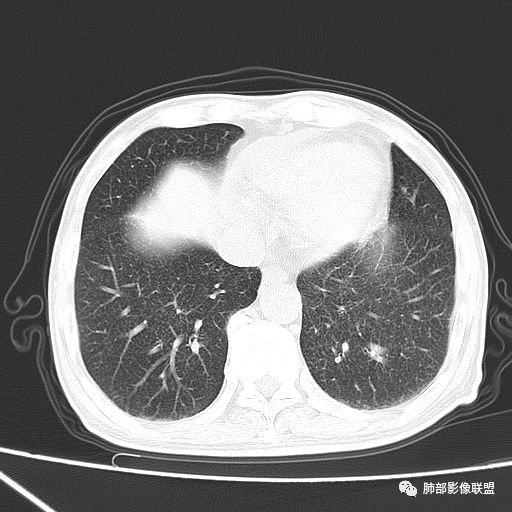

2019-10-20复查CT如下:

两肺弥漫性粟粒样结节伴左上肺小结节,呈三均匀分布,有结核的临床表现,支持血性播散性肺结核。

大小、分布均匀,边缘清楚

细小结节,弥漫,撒米粒样——血道来源

血道来源的病灶,均匀、细微,而且部分有分支状,都符合粟粒型肺结核

10月20日的CT其实是抗痨治疗近1月复查的CT。患者来我院后抗痨治疗体温下降,症状明显好转。

诊断:急性血型播散性肺结核

急性血行播散型肺结核  两肺广泛分布粟粒大小的结节状密度增高影,具有大小均匀、分布均匀、密度均匀的典型“三均匀”特征,注意急性血播病灶非常小,一般粟粒影直径1~2mm。

病灶密集者出现肺外围血管影不清或减少。

发热初期肺部可缺乏典型影像学改变,1到2周后出现的广泛粟粒结节对诊断具有高度提示作用!